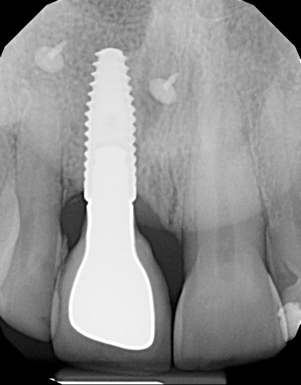

A 56-year-old female patient was referred for the evaluation of tooth No. 8 (Figure 4 and Figure 5). A periapical radiograph indicated that the tooth had undergone apicoectomy and received an excessively long post (Figure 6), and a cone-beam computed tomography (CBCT) scan of the site revealed a lack of buccal plate bone (Figure 7).

(7.) Pretreatment CBCT scan.

Figure 7